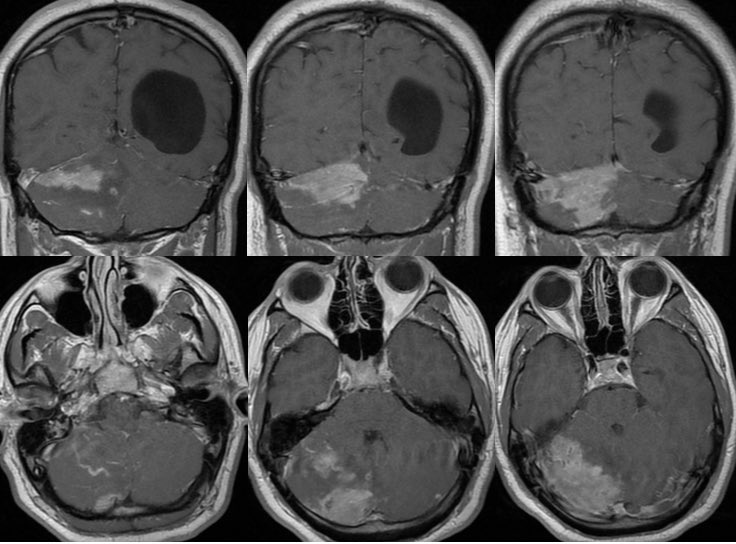

MRI: Enlarged or swollen right cerebellar hemisphere

T1: Hypointense with curvilinear high signal (slow flow in vessels)

T2: multiple tortuous flow voids and extensive edema but PRESERVED FOLIA

T1C+: bizarre somewhat geographic enhancement of the parenchyma and leptomeninges

MR perfusion shows increased CBV within the enhancing components